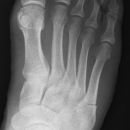

Metatarsale 5